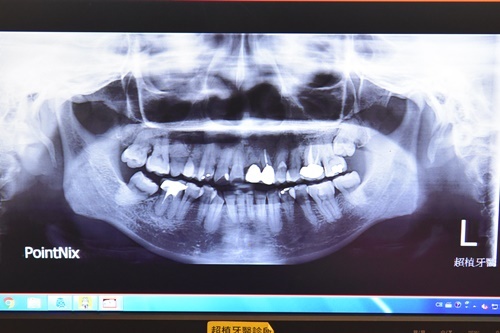

透過X光可以稍微看到老爸因為年事已高

牙槽骨密度不足~假設要做人工植牙可能還要做補骨粉的動作

就無法採用微創植牙手術來治療

老爸多年前右側下方牙橋假牙鬆動得厲害

導致他習慣依賴用另一側的假牙飲食

兩側裝了將近三十年的牙橋牙齒內部早已有蛀牙

老爸目前口腔裡面兩個牙橋以右下方的牙橋問題比較嚴重

兩側牙根有傾斜狀態加上牙柱有蛀牙情況才會鬆動

假如真得經濟能力夠想治療的話可以將傾斜兩側牙齒矯正後再做人工植牙

而原本牙橋的牙柱就得另外做全瓷冠牙套套住做保護